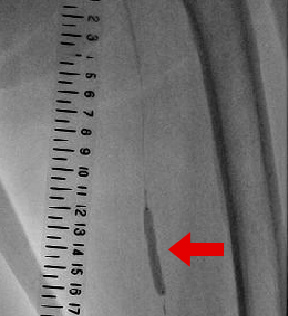

下肢動脈の病気を治療する方法です。下肢の重症虚血や間欠は行のある方の症状改善を目的に行います。下肢動脈の狭窄部分や閉塞部分に細い針金を通して、風船(バルーン)で病変を開大させます。体表からの超音波検査や血管内からの超音波検査と組み合わせて安全に治療していきます。

腎臓の機能が低下した方では、造影剤を使うことによってさらに腎臓の機能を悪くしてしまう危険があります。また、造影剤にアレルギー反応のある方も、重篤な副作用を引き起こす可能性があります。当院では通常使用する造影剤のほか、腎臓への負担を軽減するため、体に無害でアレルギー反応のない医療用炭酸ガスを用いて安全にカテーテル治療を行う技術があり、積極的に行っています。